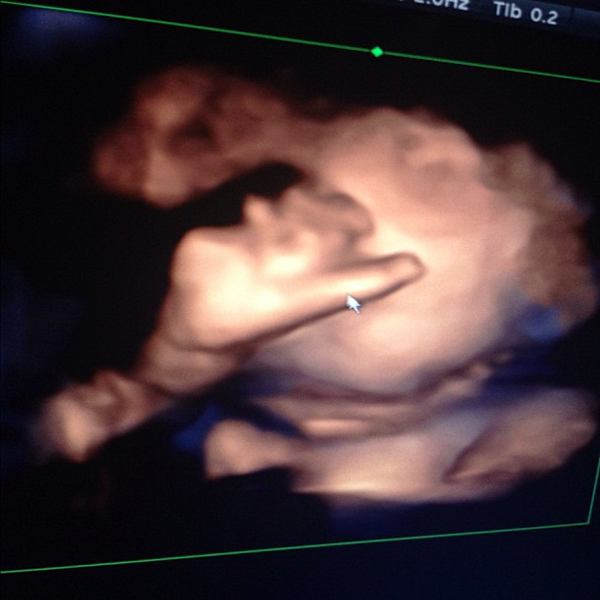

ชมกันชัด ๆ ภาพอัลตราซาวด์ หน้าลูกชาย ป๋อ ณัฐวุฒิ - เอ๋ พรทิพย์

ล่าสุด(28 มกราคม) ป๋อ - เอ๋ ก็ได้พากันไปอัลตราซาวด์ แบบ 4 มิติ หวังจะได้เห็นหน้าลูกชายแบบชัด ๆ ซึ่งก็ต้องลุ้นกันอยู่นานทีเดียว เพราะลูกชายของ ป๋อ ณัฐวุฒิ และ เอ๋ พรทิพย์ ไม่ยอมให้คุณพ่อคุณแม่เห็นหน้าง่าย ๆ เพราะเจ้าตัวคว่ำหน้าตลอด แต่ในที่สุด ลูกชายของ ป๋อ - เอ๋ ก็ยอมให้เห็นหน้าจนได้ แต่ก็ยังเอามือปิดหน้า แถมมีสายรกพาดหน้าอีก แต่แค่นี้ คุณพ่อป๋อ กับ คุณแม่เอ๋ ก็ชื่นใจสุด ๆ แล้วล่ะ